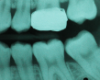

In 1998, a 7-year-old boy was brought in for emergency care with the chief complaint of toothache of the mandibular left permanent first molar. The malformed tooth was non-restorable and extracted, with no other treatment options. The child was not returned for continuing routine care but was returned on an emergency basis in 1999. He had a dentoalveolar abscess of the severely carious maxillary left permanent first molar, and the tooth was judged non-restorable (Figure 28). That molar was extracted. The patient was not returned to the office again until 4 years later, in 2003. The maxillary second molar had migrated into good position distal to the second premolar, and the third molar followed into place (Figure 29). The mandibular second molar was tipped mesially, followed by the crown of the third molar. Four years after that (2007), the patient returned as a 15-year-old. The second and third molars had migrated into position, with no orthodontic intervention (Figure 30).

Molar migrations after loss of first molars, 8-year history: 1999

Figure 28

Molar migrations after loss of first molars, 8-year history: 2003

Figure 29

Molar migrations after loss of first molars, 8-year history: 2007

Figure 30